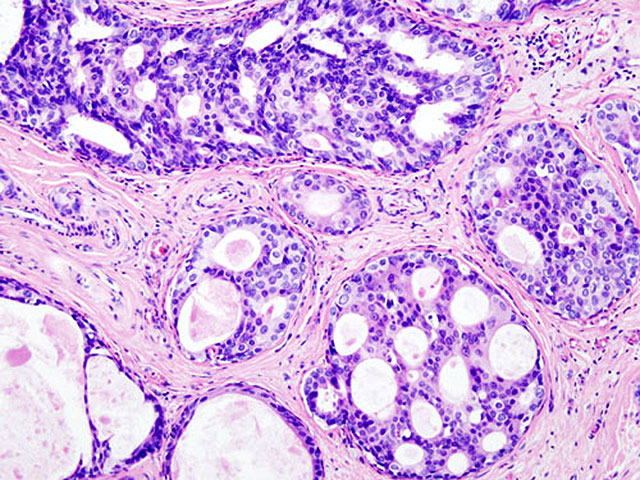

Тест BRCA предназначен для выявления генетических мутаций, которые могут значительно повысить риск рака молочной железы и яичников.